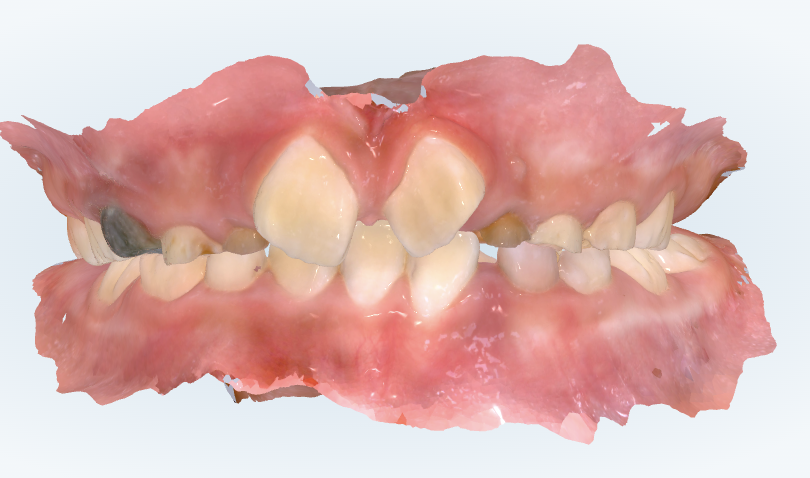

初診時の画像診断

上下の歯並びにガタガタがあります。顎の横幅が狭いです。

下の前歯が内側に倒れることで、上下の前歯の前後的距離が大きくなり、出っ歯さん傾向があります。